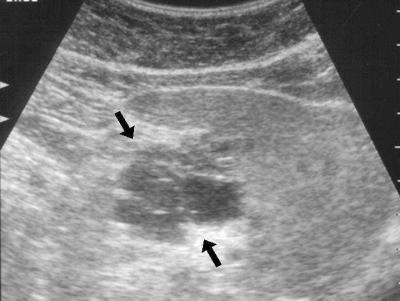

Эхогенность поджелудочной железы может быть повышена как локально, так и диффузно.

Локальное повышение указывает на наличие уплотнения в определенной области железы. Это может быть связано с опухолью, метастазами, образованием камней (которые также могут возникать в поджелудочной) или отложением кальция (обызвествлением) в местах предыдущего воспаления.

Диффузное повышение эхогенности может свидетельствовать о следующих состояниях:

Эхогенность поджелудочной железы в нормальном состоянии будет однородной. А вот при панкреатитах (остром, хроническом), при гипертензии портальной эхогенность паренхимы железы увеличивается. Если размер данного органа не увеличен, а эхогенность поджелудочной железы повышена, это может свидетельствовать о липоматозе, когда часть ее тканей замещается жиром. Иногда такая болезнь возникает у пожилых пациентов с сахарным диабетом.

При уменьшении размеров железы такие диффузные изменения могут говорить о фиброзе, то есть замещении тканей железы фиброзной (соединительной) тканью. Чаще всего это происходит, когда человек перенес воспаление в поджелудочной железе либо у него нарушен обмен веществ.